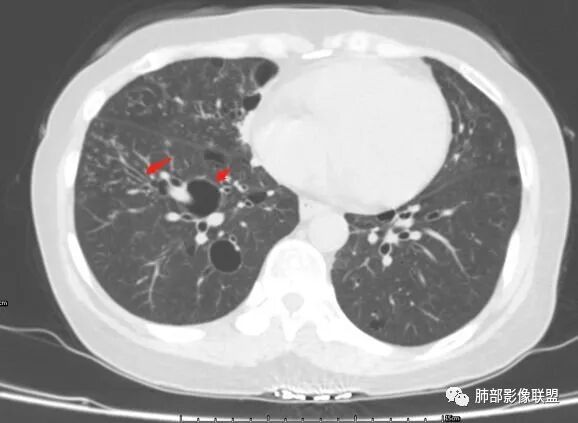

胸CT:1.双肺多发囊性变,以中下肺为主,病变边缘可见肺动脉,部分囊内可见分隔及肺动脉,双下部分肺野周围可见小叶中心结节及树丫征。

患者中年女性,因右眼红痛1天就诊。胸CT:双肺多发囊性变及结节影,囊以中下肺为多,部分囊内可见分隔及肺动脉,结节部分为实性,部分为混合性,边缘光滑,未见明显毛刺、棘突、胸膜牵拉及血管集束征象。双中下可见支气管扩张及树丫征。淋巴结无明显肿大。综合考虑:一元淋巴细胞间质性肺炎。多元鉴别肺腺癌并转移等恶性病变。

左肺下叶混杂密度病灶,其内可见空泡,周围ggo清楚,考虑浸润性腺癌。双肺散在多发薄壁囊腔和实性结节,以胸膜下及血管旁分布位于,气囊可见血管贴边征,双肺小叶间隔及中央间质增厚,局部可见磨玻璃影及树芽征,纵隔内淋巴结肿大,考虑LIP

综上,考虑左下肺浸润性腺癌+LIP

双肺多发大小不等囊腔,可见薄壁,部分囊腔内可见血管影,伴双肺多发结节,结合患者眼病及类风湿病史,考虑LIP可能大。另左肺下叶磨玻璃结节,边界清晰,内可见空泡,伴纵膈多发肿大淋巴结,不除外浸润性腺癌可能。